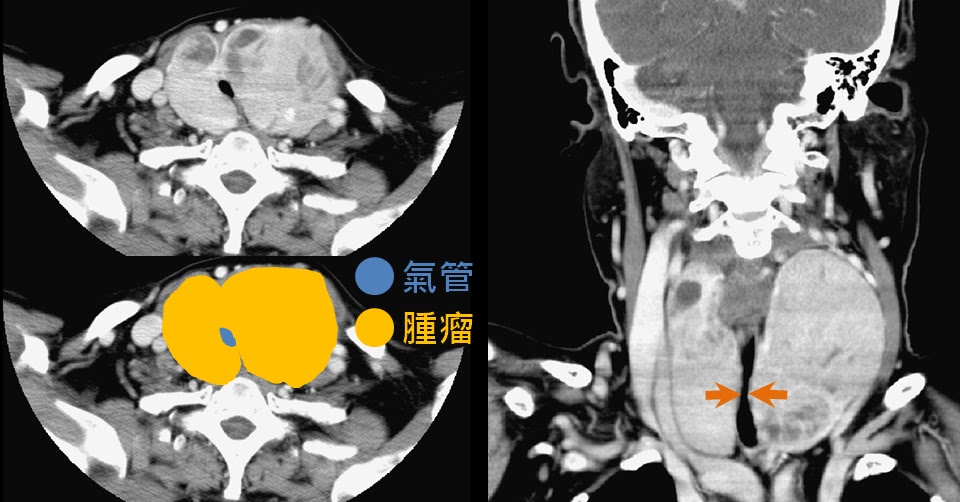

甲狀腺腫瘤如果長的比較大會壓迫到周邊的組織,例如氣管或者是食道,前者會造成呼吸不順、後者則是會影響到食物的吞嚥。以下2個案例皆是原本位於中央的氣管被左邊的甲狀腺腫瘤推向右邊,並且造成氣管管腔狹窄。

這個患者兩邊的甲狀腺都很大,左右夾擊之下,氣管只剩下一個小洞。